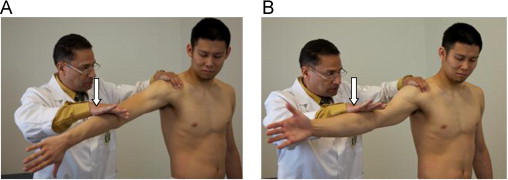

Supraspinatus weakness test - empty can/ full can (purpose, how, positive sign)

purpose - injury / weakness to supraspinatus

how- arm at 90 degrees forward flexion, thumbs up, downward pressure is applied

positive sign - pain/ weakness/ strength difference between arms